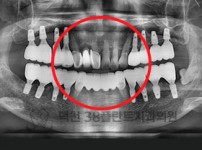

치료전후